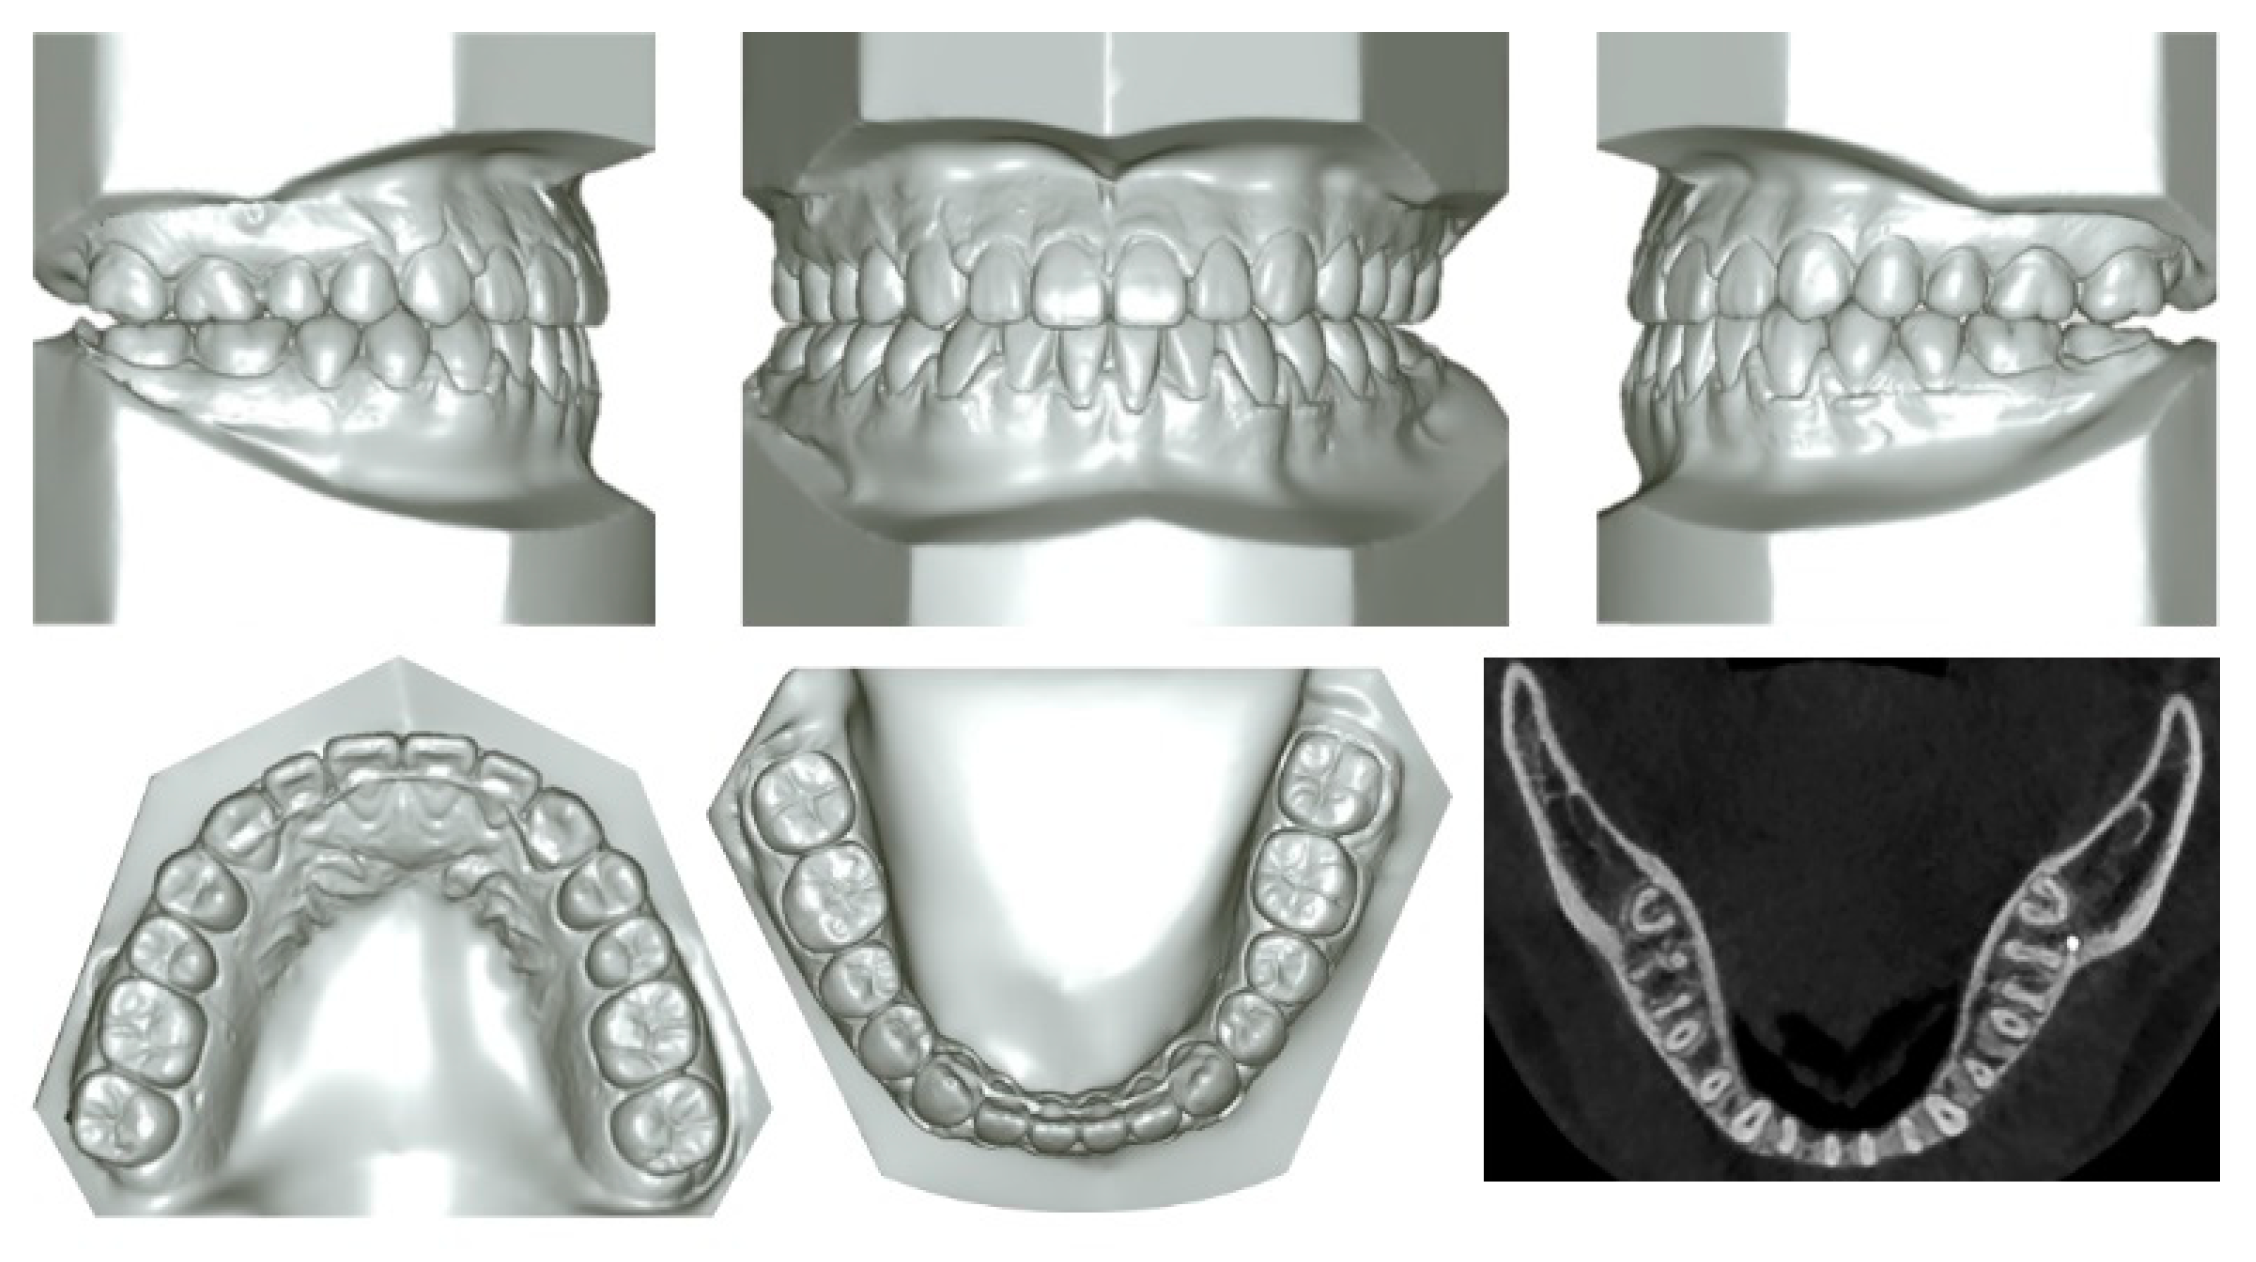

2.1. Diagnosis and Etiology

2.4. Treatment Progress